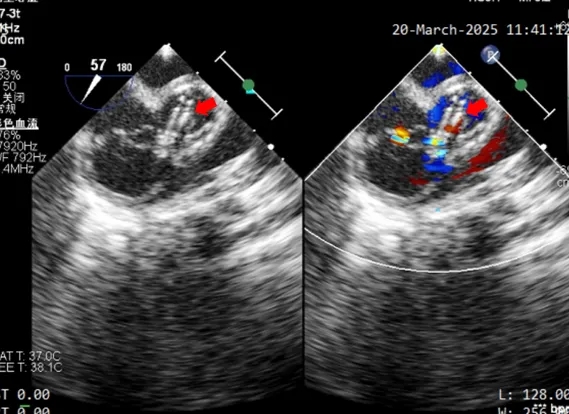

术中超声复测

膨出瘤基底部宽约7.6mm

两处破口分别宽约2.3mm及1.3mm

前顶鞘管固定钢缆,牵拉成型线进行锁定,锁定后超声

可见封堵器盘面平整,形态稳定